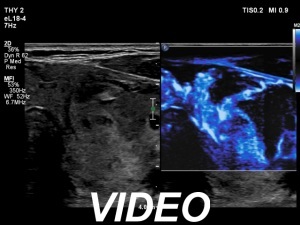

Ultrasonography. The thyroid was echonormal. The right lobe contained several discrete areas without any clinical significance. There was multi-chambered cystic nodule in the left lobe. The nodule had echonormal solid part and presented halo sign.

- The cyst has just started refilling after the evacuation.